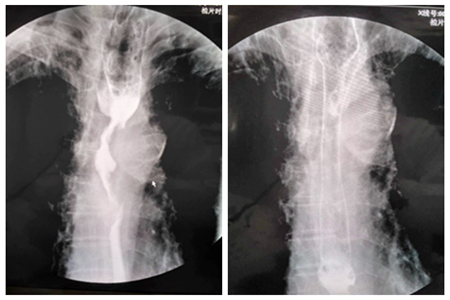

患者5,女,66 ,食道远端及贲门癌

放置支架后对比图